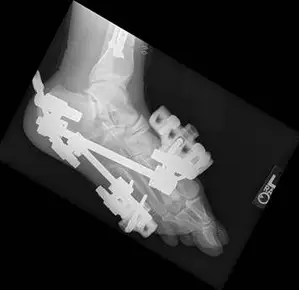

In the x-rays below there are fractures seen in the midtarsal bones that can occur with a high impact twisting injury where the foot is caught in something like the stirrup of a horse saddle or from direct high impact traums to the middle of the foot. The fractures can be seen from a view at the top of the foot (left) and side of the foot (right). This injury requires open reduction with internal fixation in order to re-align the fractured bones and prevent disability (Bottom left).

These are pics of the external fixator on to hold temporary reduction prior to internal fixation